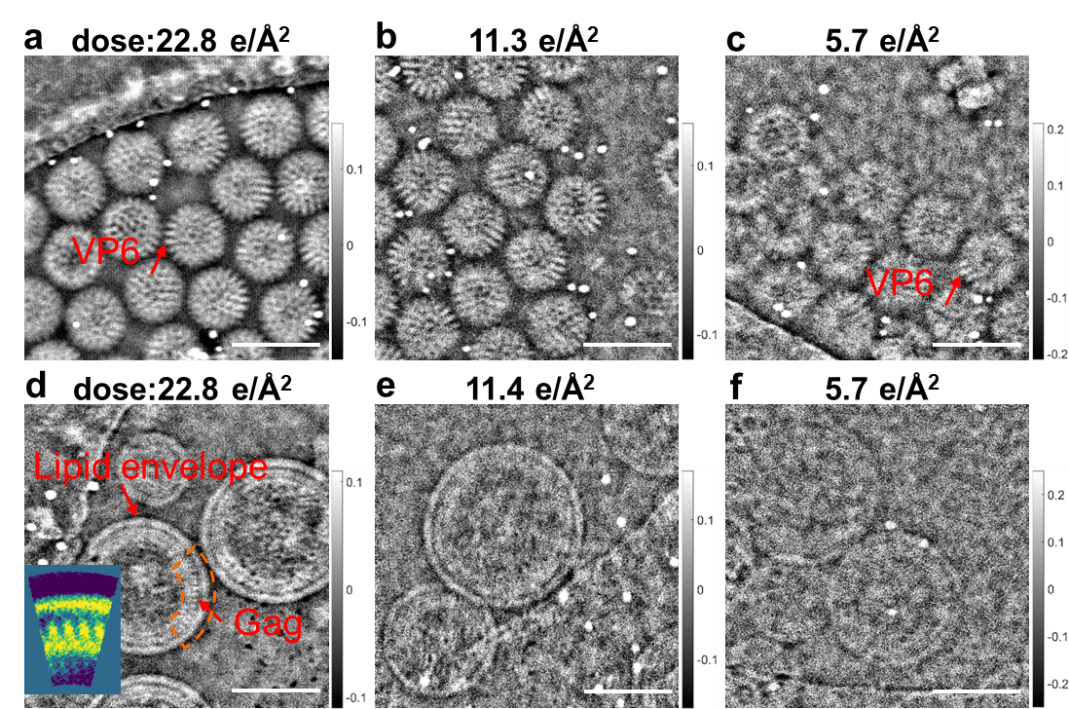

如图2所示分别为不同电子剂量条件下DLPs及HIV-1病毒颗粒的冷冻叠层成像相位图像。对于DLPs,在电子剂量条件为22.8 e/?2(图a)时,DLPs 颗粒衬度高,颗粒上VP6 蛋白衬度清晰明锐,多个蛋白质颗粒围成的通道清晰可见;随着电子剂量的降低,颗粒衬度有所减弱,但即使在超低电子剂量5.7 e/?2的条件下,病毒颗粒衬度依然可见,颗粒上VP6 蛋白依然具有明显衬度(图c)。对于HIV-1,电子剂量条件为22.8 e/?2(图d)时,病毒颗粒细节衬度高,病毒颗粒中包膜(Lipid envelope)及Gag蛋白颗粒衬度明锐;即使在超低电子剂量5.7 e/?2的条件下,病毒颗粒衬度依然清晰可见。

图2 不同低电子剂量条件下DLPs及HIV-1病毒颗粒的原位冷冻叠层成像相位像 (a-c)DLPs; (d-f) HIV-1;d内小插图为弧形区域的平均结果;图中标尺为100 nm